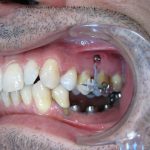

Après traitement orthodontique et réalisation d’une attelle fibrée (courtoisie Dr Patrick Fournier)